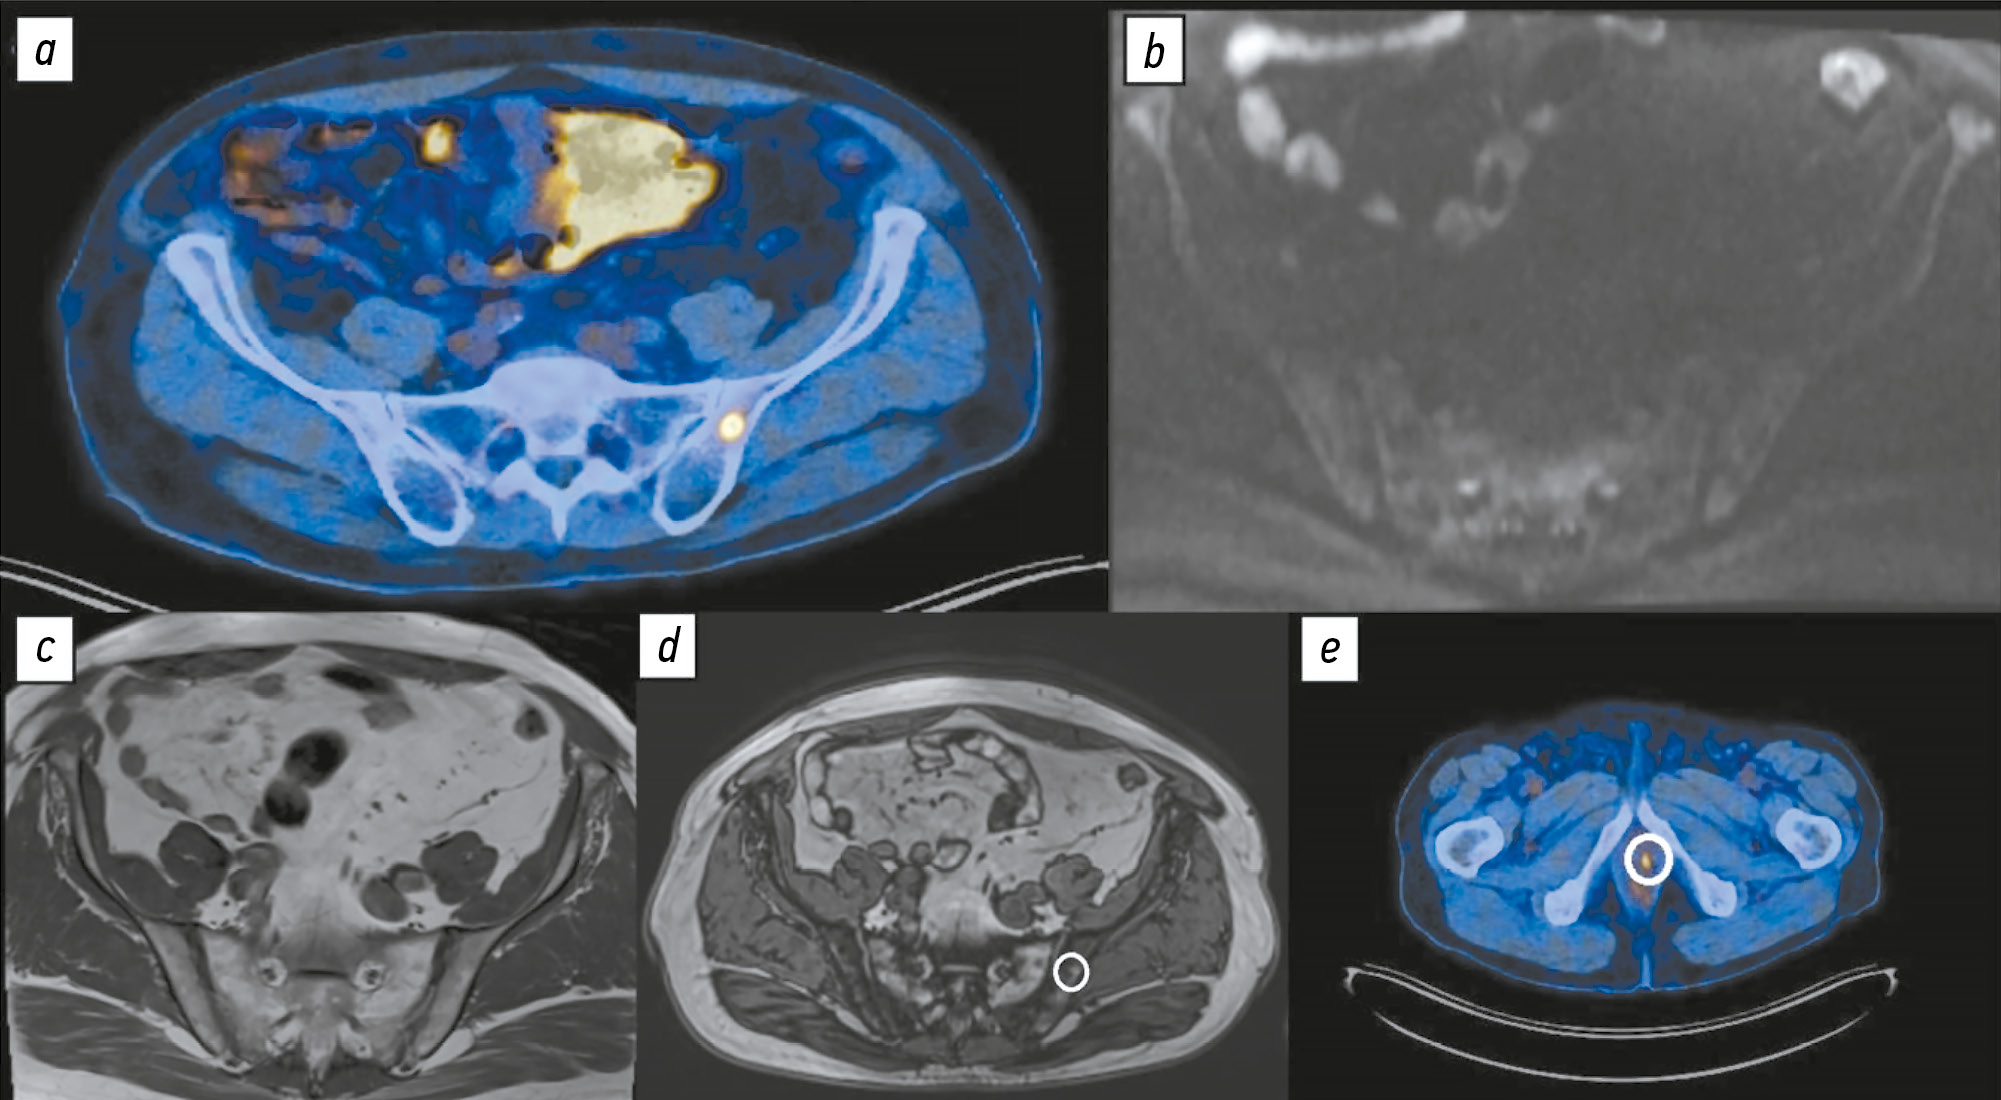

Comparison of the diagnostic accuracy of whole-body diffusion-weighted imaging and 18F-prostate-specific membrane antigen-1007 positron emission tomography combined with computed tomography for detecting bone metastases in prostate cancer

Abstract

BACKGROUND: The increasing availability of 18F-prostate-specific membrane antigen-1007 (18F-PSMA-1007) for prostate cancer staging highlighted its advantages, particularly its higher spatial resolution compared to analogs. Moreover, accumulating scientific data indicate an increase in false-positive findings, predominantly in bones, which may lead to unwarranted upstaging of the disease. Diffusion-weighted imaging may be used for the early detection of bone metastases.

AIM: This study aimed to assess and compare the diagnostic accuracy of whole-body 18F-PSMA-1007 positron emission tomography combined with computed tomography and whole-body and pelvic bone diffusion-weighted imaging in patients with prostate cancer.

METHODS: A retrospective single-center selective study was conducted. The imaging results of 119 patients with prostate cancer were divided into two groups: group 1 comprised 40 pairs of 18F-PSMA-1007 positron emission tomography combined with computed tomography and whole-body diffusion-weighted magnetic resonance imaging scans, and group 2 included 79 pairs of similar studies, with magnetic resonance imaging performed only for the pelvic bones. The diagnostic studies were performed at an inter-study interval ≤14 days. The metastatic bone lesions detected in different anatomical regions was counted using data from 18F-PSMA-1007 positron emission tomography combined with computed tomography and magnetic resonance imaging. Lesions were considered true positives if confirmed by additional magnetic resonance imaging pulse sequences and/or follow-up observation.

RESULTS: Whole-body diffusion-weighted imaging demonstrated higher specificity (58.1%) for detecting bone metastases than 18F-PSMA-1007 positron emission tomography combined with computed tomography (51.06%). However, its sensitivity was lower: 93.22% versus 97.55%.

CONCLUSION: Despite its advantages, 18F-PSMA-1007 positron emission tomography combined with computed tomography shows a high rate of false-positive bone findings. These are most commonly noted in the ribs, vertebrae, and pelvic bones. Suspicious bone lesions should be further evaluated to avoid unjustified disease upstaging. Thus, whole-body magnetic resonance imaging with diffusion-weighted sequences and selective fat signal suppression can be used.

239-250